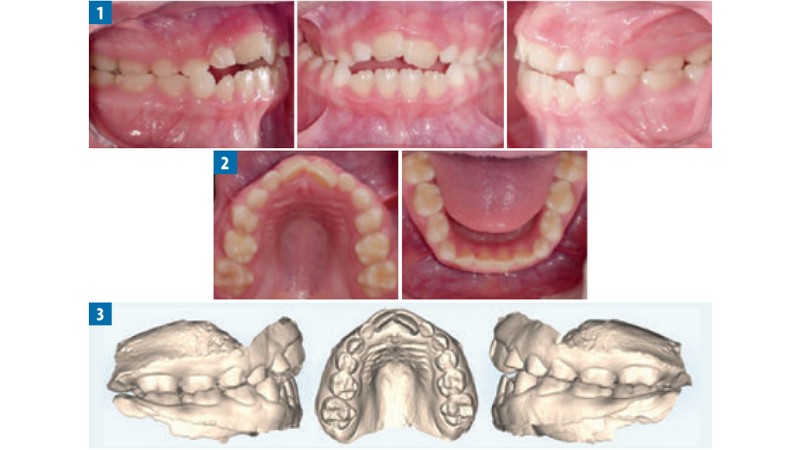

Streszczenie: W artykule przedstawiono przypadek leczenia pacjentki ze stwierdzonym obustronnym zgryzem krzyżowym bocznym oraz nakładającymi się siekaczami i zgryzem otwartym za pomocą ekspandera podniebiennego Invisalign®.

Summary: The article presents a case of a patient with bilateral lateral crossbite, overlapping incisors and open bite treated with the Invisalign® palatal expander.